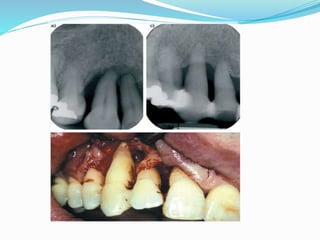

CLINICAL FEATURES

 Supra and subgingival plaque accumulation

(frequently associated with calculus)

 Gingival inflammation

 Pocket formation

 Loss of periodontal attachment

 tooth Mobility in advance cases.

 Furcation involvement

 Occasional suppuration

 Blunted or rolled gingival margins and Flattened or

cratered papillae.

 Gingival bleeding- either spontaneous or in response

to probing.

 In some cases, due to long standing, Low grade

inflammation, thickened fibrotic marginal tissues

may obscure the underlying inflammatory

changes.

 Both horizontal and vertical bone loss is evident

radiographically.

Radiographic signs

 The following characteristic are indicative of periodontal tissue

change.

 1. The crest of interdental bone will be 2 mm or more apical to the

CEJ; this is very important to determine if there is bone loss.

 2. The crest of alveolar bone will appear fuzzy in appearance.

 3. Lamina dura will be ill-defined .

 4. Density of interdental bone will be decreased .

• 5. Furcation areas of molar areas will be involved, and you

will find radiolucency in that area.

Pattern of bone loss may be vertical or horizontal

VERTICAL HORIZONTAL